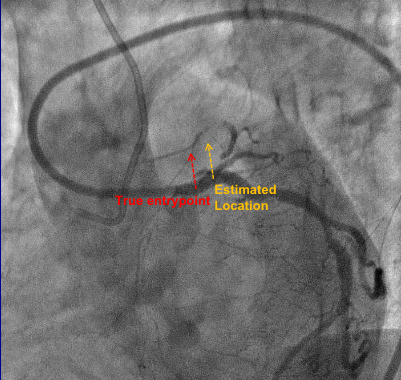

结合IVUS图像确认穿刺点及穿刺方向

Discrepancy

• The distance between the true (IVUS-determined) and estimated (angiographic) cap location was 1.9±2.7mm by an experienced interventionalist or 2.8±2.8mm by an inexperienced analyst, p<0.001.

• 经验丰富的CTO术者,在单纯以造影来判断无残端CTO的Entrypoint时,其中有近30.5%的病例与IVUS有判断的Entrypoint距离在1.5mm以上,这种情况可能会导致前向穿刺的失败甚至不良并发症的发生。